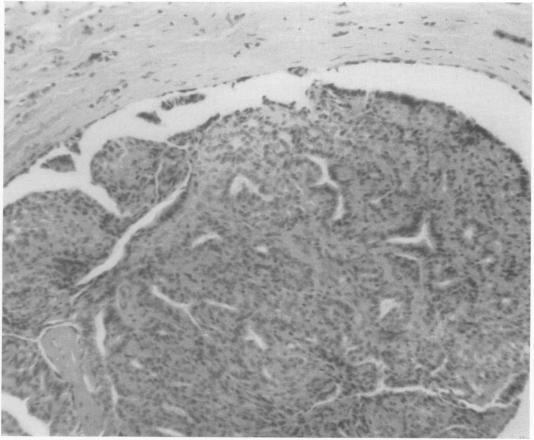

Can breast carcinoma be anticipated? A follow-up of benign breast biopsies.

Ann Surg. 1968 Jun;167(6):829-38. doi: 10.1097/00000658-196806000-00003.